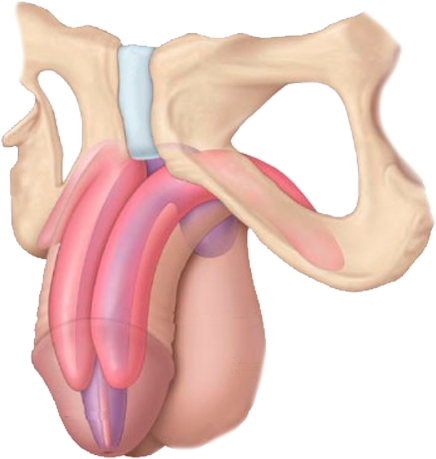

Tengo como compromiso mejorar la salud de nuestra comunidad y promover la prevención de patologías que afectan al aparato urinario, glándulas suprarrenales y retroperitoneo de ambos sexos, y el aparato reproductor masculino.

El Dr. Alejandro Palmeros Rodríguez es un médico especialista en urología comprometido con el bienestar de sus pacientes. Mediante su conocimiento y el uso de tecnología puede lograr la recuperación de distintos padecimientos y lograr una vida sana.